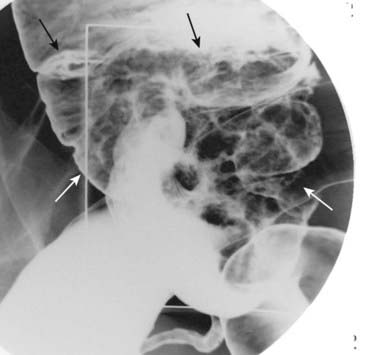

image

Figure 18-40 Massive lymphadenopathy, lymphoma.

There is massive abdominal lymphadenopathy occupying most of the abdomen (solid white arrows) and displacing the kidneys (K) laterally and the aorta (A) anteriorly far from its normal location next to the spine (solid black arrow). The patient had non-Hodgkin lymphoma.